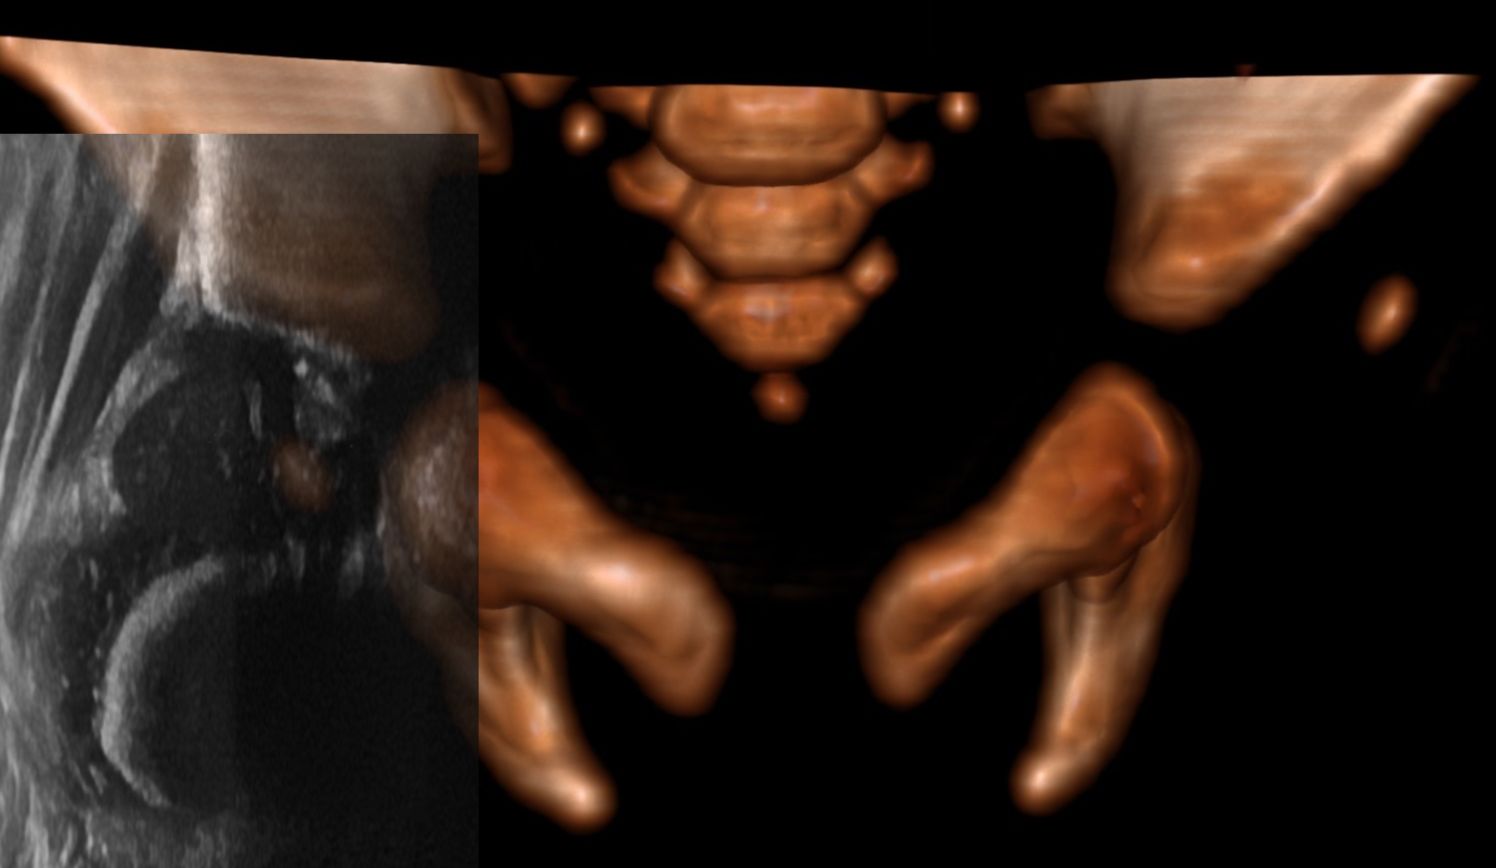

If you are scanning the right hip, rotating the probe clockwise will result in the part of the image formed by the top of the probe to raise in a curve:

And if you rotate anticlockwise, it will cause it to fall as a curve:

So to make a straight line you either chase it down by rotating anticlockwise or raise it up by rotating clockwise whilst maintaining the centre of rotation such that the structures of interest remain on screen. The opposite rotation is needed when scanning the left hip.

This page assumes the standard radiological convention of superior and rightwards structures are displayed on the left of the screen as opposed to Graf's method of flipping and rotating the images.